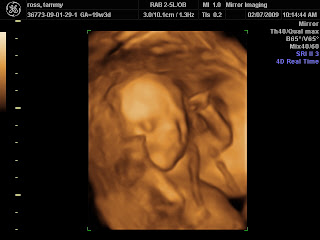

19 Week 3d Ultrasound Pictures

Oct 24 2014 explore my babys debut carla glovers board 3d ultrasound pics on pinterest. 19 weeks pregnant ultrasound pictures picture 1 shows a close up of a baby girl at 19 weeks and 3 days pregnant. Your babys development at 19 weeks. The first fetal ultrasound often scheduled between weeks 18 and 20 might amaze you by revealing the detailed development that has taken place in the last 5 months.

3d 5d ultrasound images and 4d ultrasound video can be obtained at any stage. However we do recommend a gestational age of 26 34 weeks for the best facial detail. In picture 3 as you can see the gender of the baby is revealed in the ultrasound. 19 week 3d ultrasound baby picture.

At this stage the baby has put on some weight and filled out to make features more visible yet still enough fluid in front of babys face to obtain great images. Picture 2 is an ultrasound image that shows the foot and leg of a baby girl at 19 weeks 3 days pregnant. By this time an unborn baby may also develop some hearing abilities. 5 color thermal 5 black and white.

Size and structure a fetus at 19 weeks gestation is about 6 inches measured from head to bottom what doctors call the crown to rump measurement or 10 inches from head to heel.